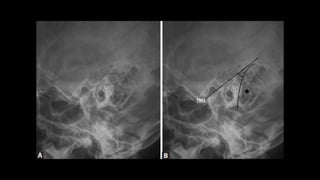

Angulated fracture of the left zygomatic arch.

z Submentovertical view  Itis an angled inferosuperior radiograph of the base of skull.  Any cervical spine pathology should be ruled out before performing this view.  If erect, patient sits and leans back head facing away from the receptor.  If supine use pillow to elevate and tilt head backwards.  The head is tilted until IOML is parallel to the receptor and the vertex is in contact with the receptor. Beam centred 4cm inferior to mental point. • collimation • anterior to include mandibular mentum • posterior to include occipital bone • lateral to include the skin margin

Angulated fracture ofthe left zygomatic arch.